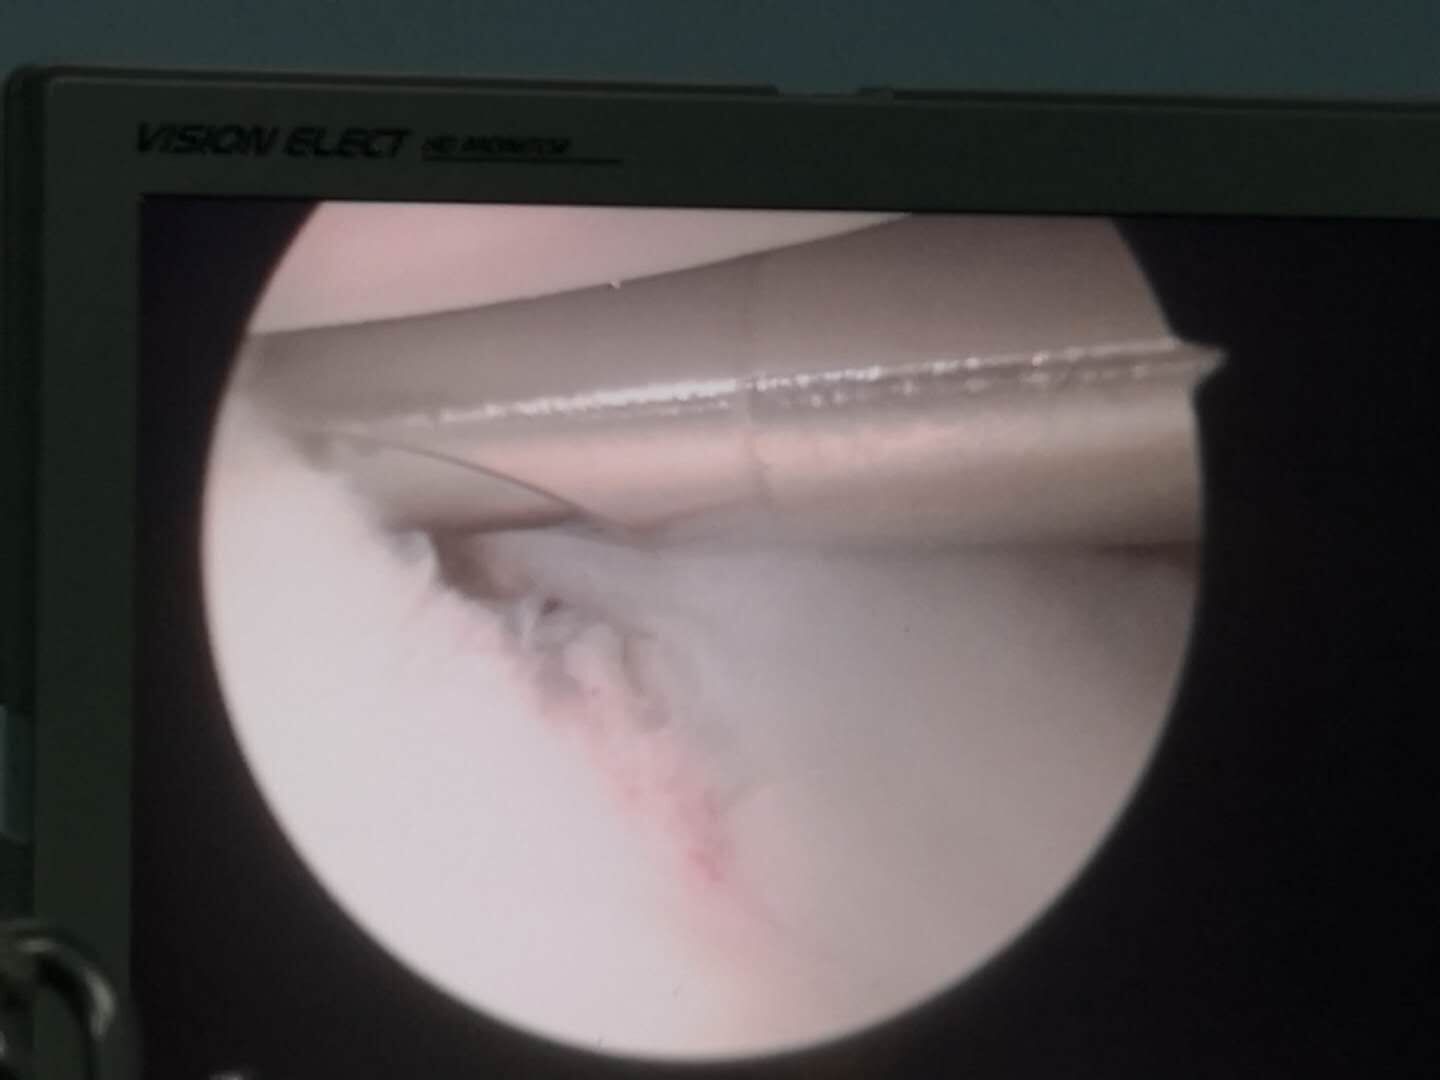

对于肩关节后方不稳的治疗,以往大多采用切开手术的方法,手术切口大,创伤重,术后容易发生肩关节粘连等并发症,治疗效果并不理想。骨外二科近几年虽开展肩关节镜治疗肩袖损伤的微创治疗,已积累了比较丰富的经验,但对于手术难度较高的肩关节后方不稳的稀少病例,还是倍加慎重,经过仔细翻阅大量文献资料,请教北京积水潭指导帮助下,手术如期进行,只在肩部切三个半厘米的小口,精准找到病变部位,经过一个多小时的肩关节镜下“肩关节盂唇修复和关节囊紧缩手术”,小陈的病痛得以根治,术后第三天小陈就出院,目前小陈的肩关节很稳定,再经过两个月左右的康复锻炼,就可恢复正常功能。